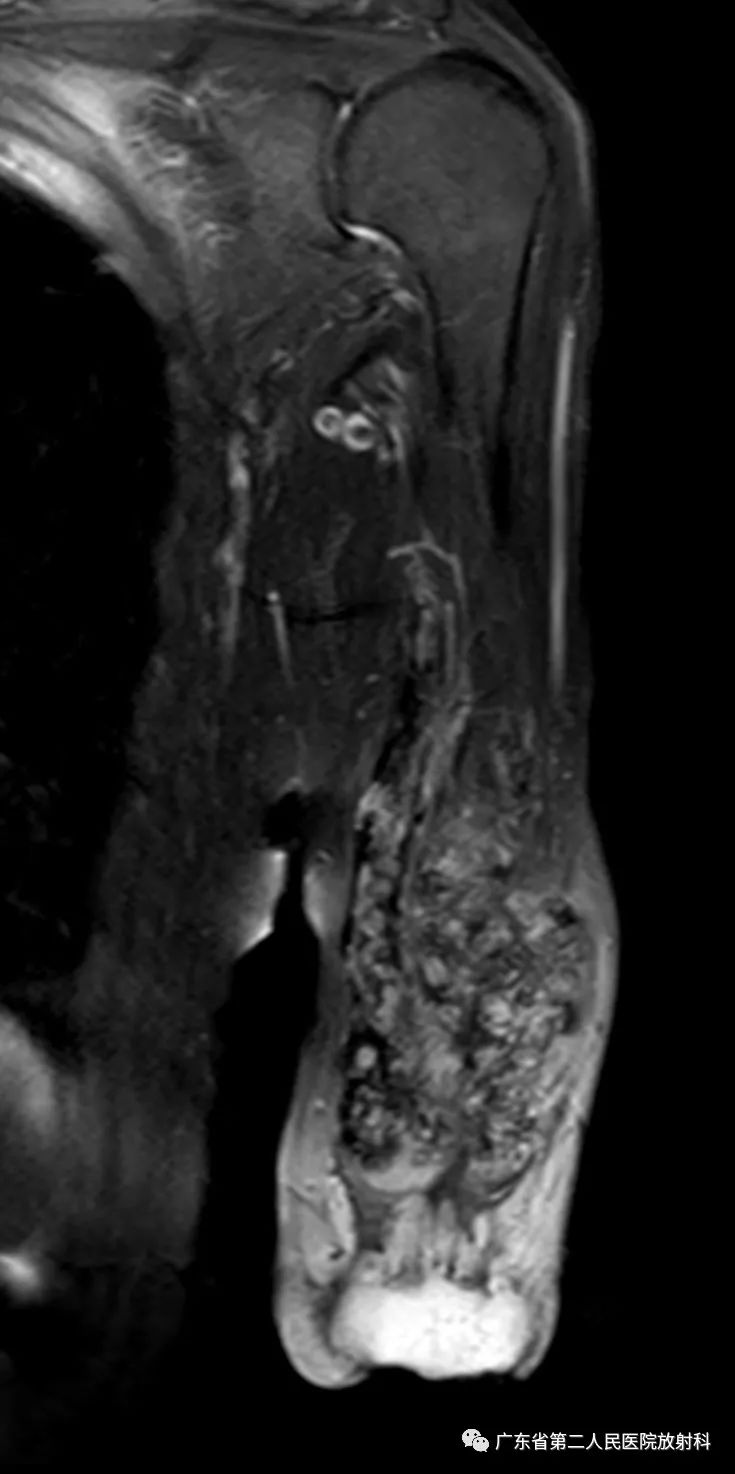

左上肢前壁截肢术后观,左上臂中下段见团块状异常信号,病灶信号明显不均,整体以长T1长T2信号影为主,增强扫描呈明显不均匀强化,末端球形膨大,内见散在少许团絮状短T2长T1且无强化信号。冠状位示病灶整体呈梭形改变,边界欠清,部分包绕肱骨下段,以长T1长T2信号为主,散在少许短T2信号,增强扫描明显不均匀强化,内见散在少许团絮状短T2长T1且无强化信号。肱骨下端边缘欠光整,骨髓未见明确异常信号。